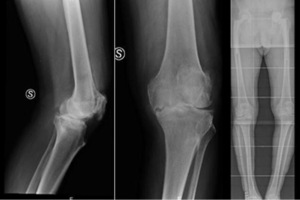

All patients were over 75 years old (mean 81.75; range, 75–89 years old), with a severe deformity: preoperative planning was made and a semi constrained TKA was performed in knees with a valgus over 15° or varus over 10° with or without collateral ligament failure. 10 of 28 knees had a valgus deformity and 18 had a varus deformity (Figure 1).

X-rays showed no radiolucent lines in all knees neither in femur nor in tibia. No component loosening or peri-prosthetic fracture was reported. At the same, there were no deep infections of the operated joints (Figure 2).